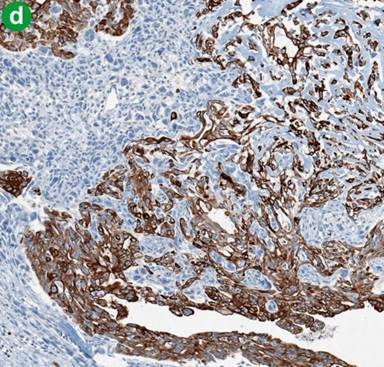

The epithelial lining of the pancreatic duct with intraductal extension of the tumor (including epithelial neoplastic component intermingled with the nonepithelial component) had a distinct immunoprofile compared to normal branches of pancreatic duct without intraluminal growth. It was positive for cytokeratin (CK) 5/6 (Cell Marque D5&16B4, Rocklin, CA, USA), p63 (Cell Marque 4A4) and p53 (Ventana Bp53-11, Tucson, AZ, USA) (Figure 4ab). Staining for CD10 (Cell Marque 56C6), estrogen receptor (Ventana SP1), progesterone receptor (Ventana IE2), and inhibin (Dako R1, Carpinteria, CA, USA; 1/50 dilution) did not reveal ovarian like stroma, ruling out the possibility of the mucinous cystic neoplasm. Common markers such as CK 7 (Dako OVTL 12/30) and CK 20 (Cell Marque K520.8) had a similar pattern of the staining in normal branches of pancreatic and pancreatic ducts with intraluminal neoplastic growth. Overall, the epithelial component was positive for cytokeratin 34 betaE12 (Ventana 34be12), pankeratin (Ventana AE1/AE3/PCK26), CK 7, CK 5/6, p63, p53, epithelial membrane antigen (EMA) (weak) (Cell Marque E29), CEA (Ventana V9) and E-cadherin (Cell Marque ECH-6), but negative for CK 20, vimentin (Ventana V9), desmin (Ventana DE-R-11), actin (Cell Marque 1A4), calponin (Dako 1/50 dilution), CD10, CD117 (Dako ckit 1/100 dilution), estrogen receptor/progesterone receptor, inhibin and alpha antitrypsin (Cell Marque polyclonal). Interestingly, the epithelial component co-expressed (at least focally) CK 5/6 and p63, indicating the squamous/transitional or myoepithelial nature of the epithelial component.

Figure 4. Comparison of the immunoprofile of the normal pancreatic duct (without intraluminal growth) with pancreatic duct involved by undifferentiated carcinoma of the pancreas. Left upper corner: normal pancreatic duct; right lower corner: pancreatic duct partially occluded by undifferentiated carcinoma of the pancreas, neoplastic epithelial component positive for CK 5/6 (a.) and P 63 (b.). (Original magnification 4x both). |

The nonepithelial components of the tumor were positive for vimentin, desmin (focally), actin, p63, p53 (focally), calponin, CD10 (focally), CD117 (focally, weak) and alpha antitrypsin and negative for cytokeratin 34 betaE12, pankeratin, CK 7, CK 5/6, CK 20, EMA, CEA, estrogen receptor/progesterone receptor, inhibin and E-cadherin. CD68 (Ventana Kp-1) was positive in the osteoclast-like giant cells and large histiocytes-like cells. Both neoplastic components (epithelial and nonepithelial, excluding osteoclast-like giant cells) were strongly positive for Ki-67 (Ventana 30-9), p63 and focally p53 (Figure 5ab). CD31 (Ventana 1A 10) and factor VIII (Cell Marque polyclonal) highlighted only the feeding vessels.